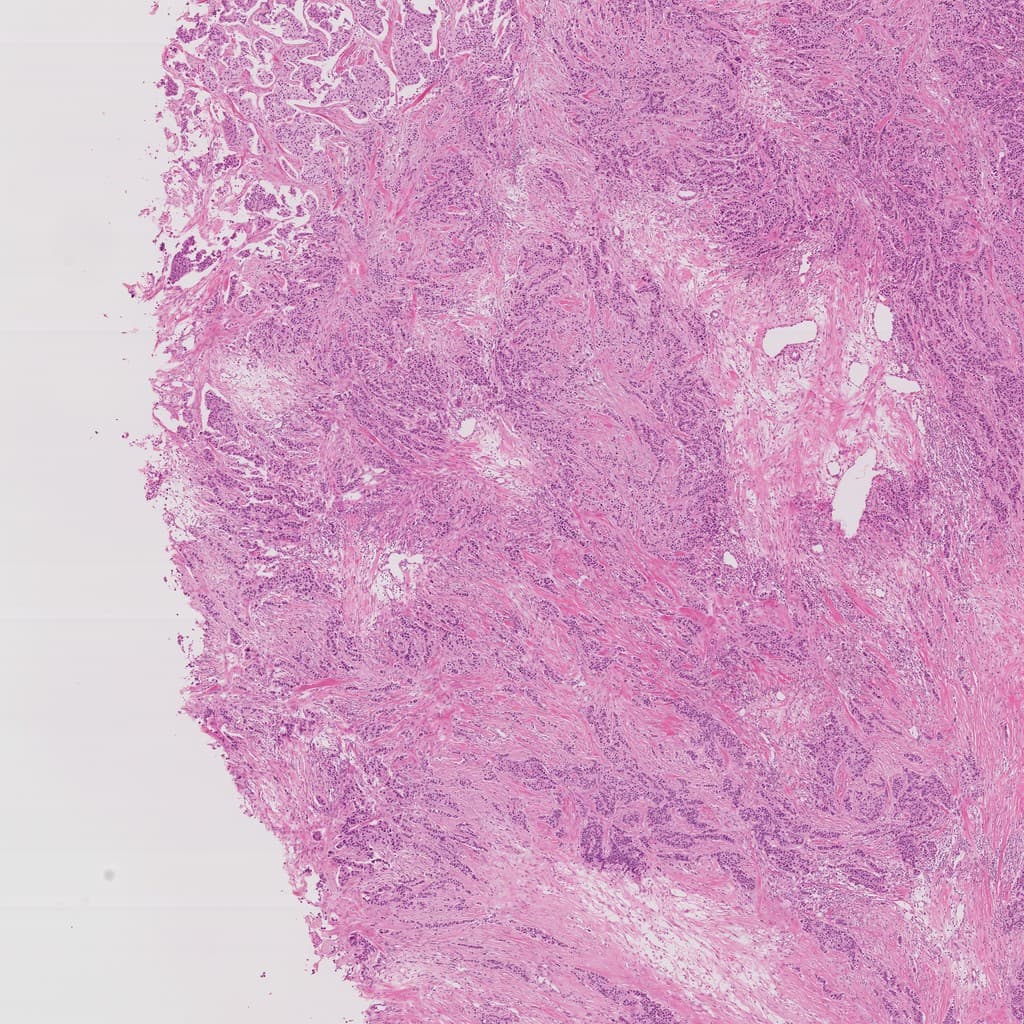

Global scan: Identify overall tissue architecture and abnormal region distribution as the starting point for multi-scale reasoning.

Whole slide image shows lung tissue specimen with large dark purple solid areas contrasting surrounding normal alveolar structures, suggesting locally high cellularity lesion.

This region shows loss of normal alveolar structures with acinar and papillary growth patterns, suggesting marginal features of neoplastic proliferation with clear diagnostic value.